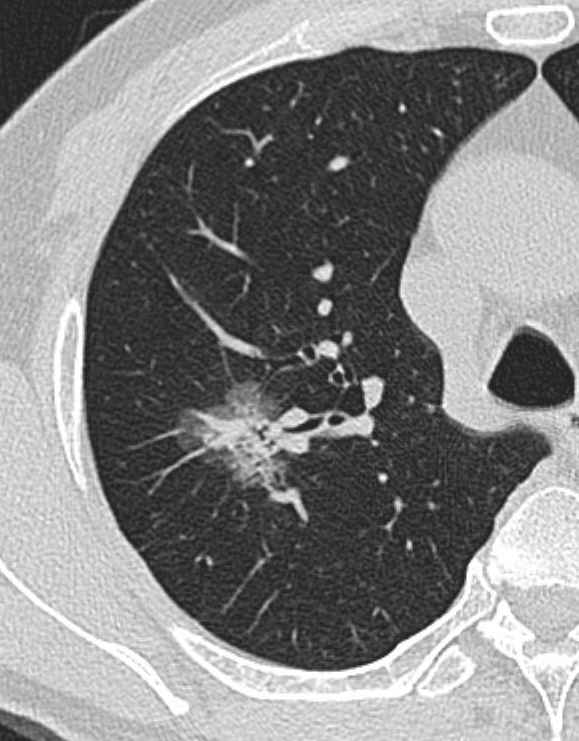

CT检查其实也是利用X射线给身体拍照片,它是为您从上到下拍很多张照片,一层一层的穿过人体检查的,因此受外物干扰小,简单来说就是看的更清晰准确

一系列照片经过计算机整合处理后,可以从多个平面观察组织结构,也可直接反映出人体骨骼的三维形态

优点:与DR相比,CT扫描出来的是断层图,器官之间无重叠且显示清晰,密度分辨率更高,可以更清晰直观地显示病变区域影像。CT检查方便、迅速而安全,且随诊方便,尤其是对于急诊病人能较快做出诊断。

缺点:CT价格高于DR,且辐射大于DR。